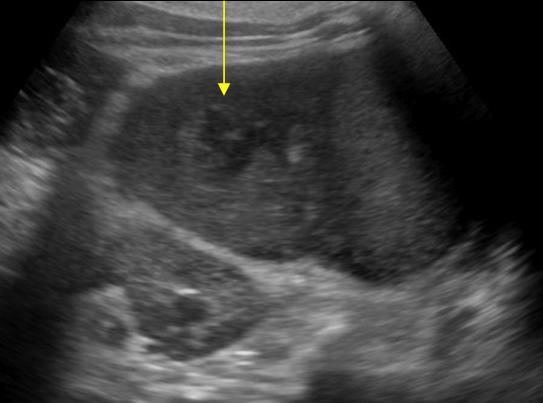

Nhồi máu lách

» Thông tin: Nam giới – 74 tuổi.

» Lâm sàng: Đau mạn sườn trái.